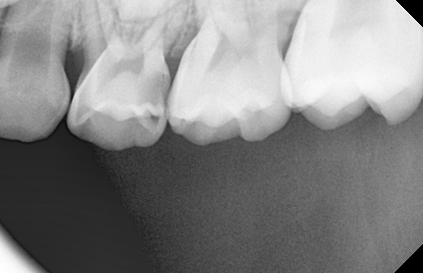

건강한 영구치는 건강한 유치에서 시작됩니다.

유치는 영구치보다 충치의 발생빈도 및 진행속도가 빠릅니다.

아이의 구강 상태에 맞는 소아 충치치료가 필요합니다.

충치의 깊이가 얕을 경우 GI 또는 레진으로 수복치료를 하게 되며,

충치의 깊이가 깊을 경우 신경치료 후 크라운치료(은니)를 하게 됩니다.